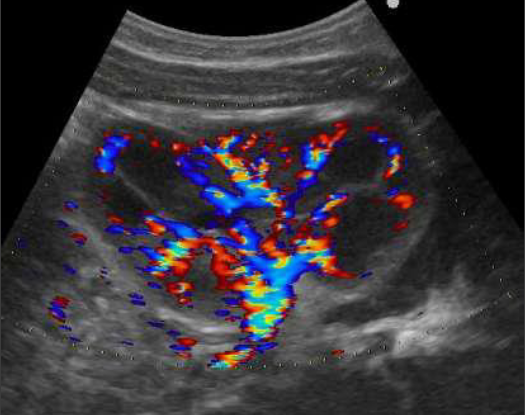

Imagerie des infections urinaires et du reflux vésico-urétéral

• Imagerie des infections urinaires et du reflux vésico urétéral - 1ère partie

• Imagerie des infections urinaires et du reflux vésico urétéral - 2ème partie